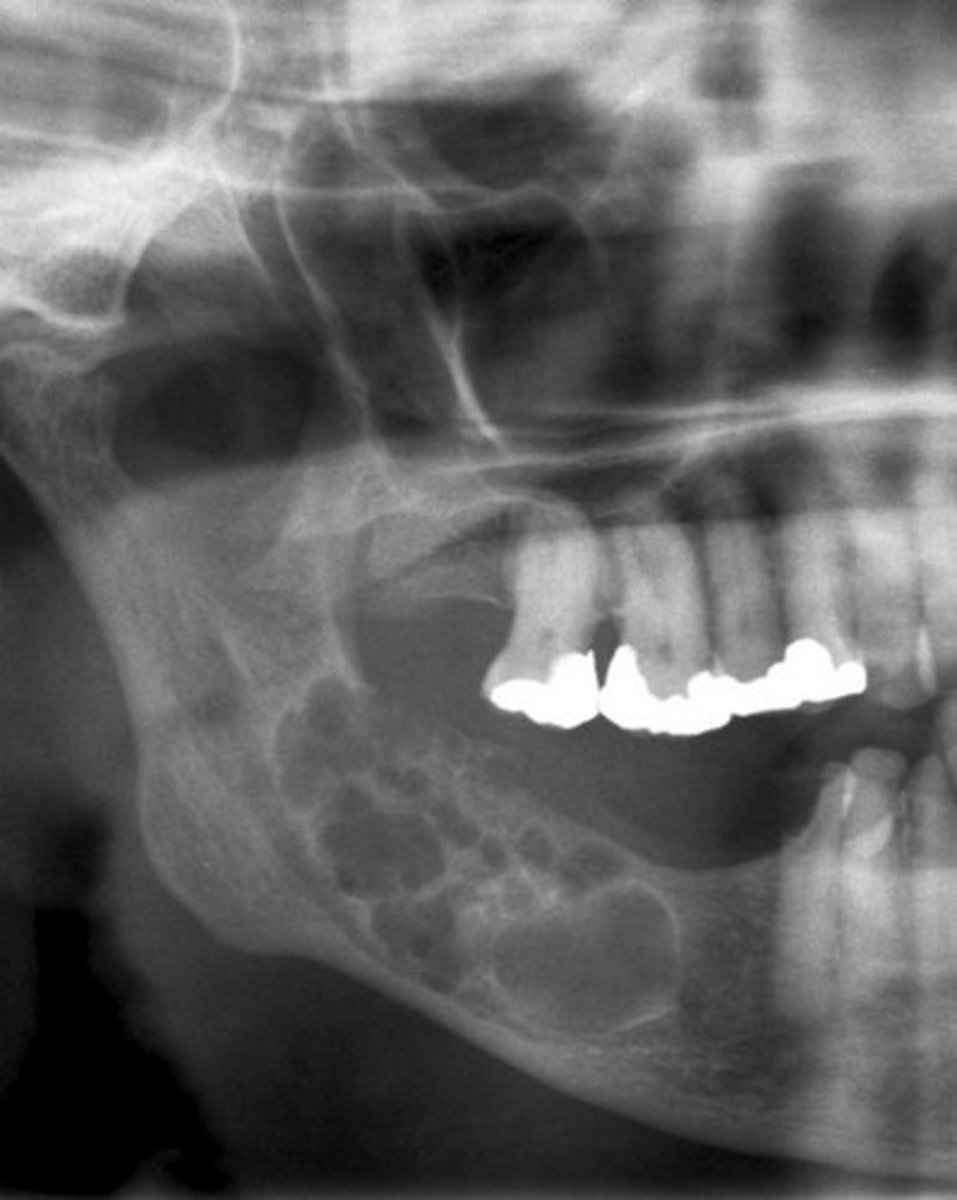

what is this?

what is this radiolucent area in the image?